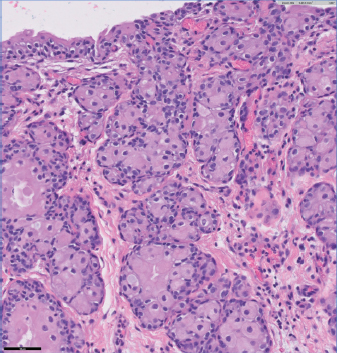

Lesion 1 as seen in Figure 1, embedded within the suppurative inflammation of the ventral bladder wall’s muscularis layer was a plant foreign body. The inflammation is associated with reactive fibrosis and peripheral lymphofollicular aggregates. Peripheral portions of the inflammation also have heavy aggregates of hemosiderosis and multifocal acute hemorrhage.

Fig. 1. Plant foreign body was embedded within the suppurative inflammation of the ventral bladder wall’s muscularis layer. The inflammation is associated with reactive fibrosis and peripheral lymphofollicular aggregates. Peripheral portions of the inflammation also have heavy aggregates of hemosiderosis and multifocal acute hemorrhage.